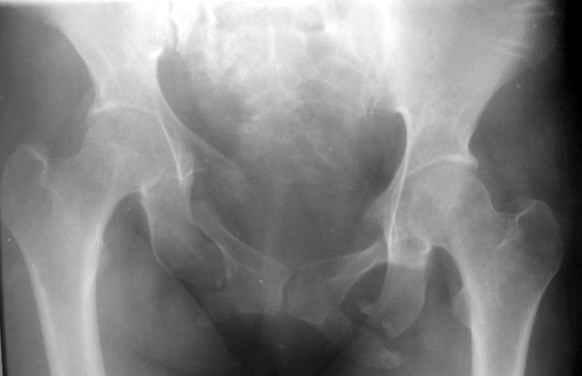

Привожу пример лечения больного с 7 месячной деформацией. Отеотомии - аппарат - внутренняя фиксация.

Рентгенограммы до и через месяц после окончательной стабилизации. Потом поищу более поздние снимки.